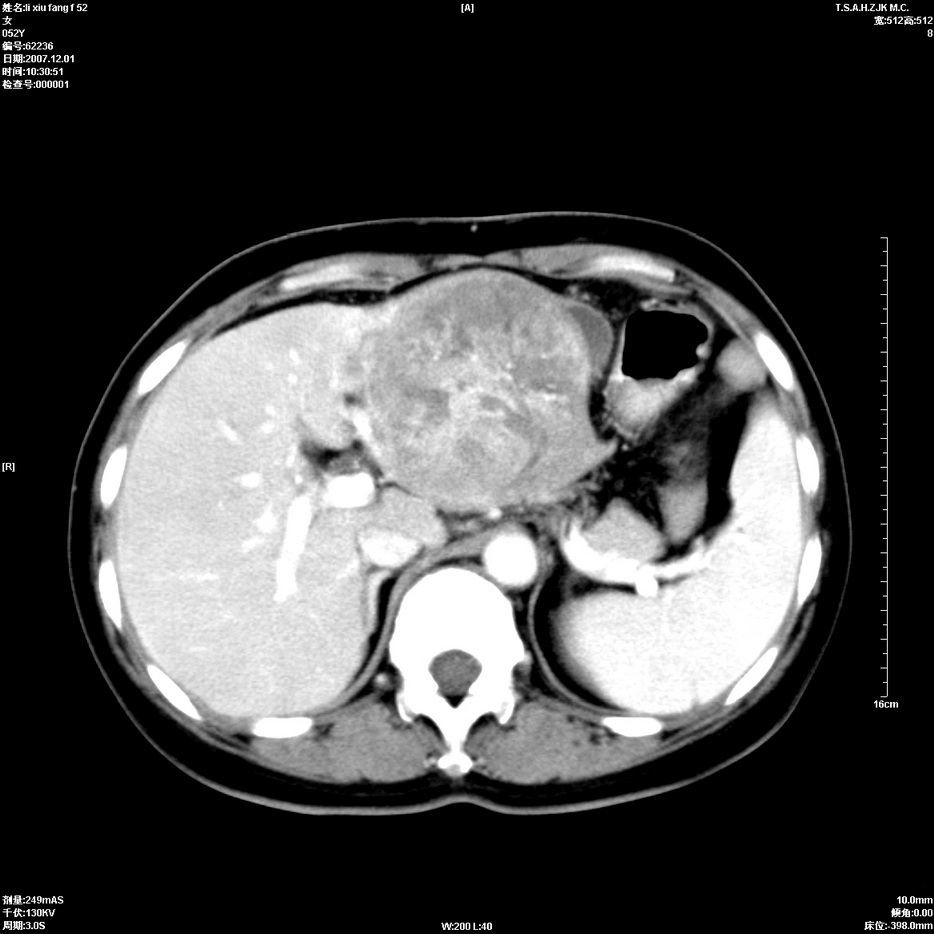

标题: CT12858:女,52岁,胎甲球蛋白861肝左叶占位,肝癌。下腔静 [打印本页]

标题: CT12858:女,52岁,胎甲球蛋白861肝左叶占位,肝癌。下腔静

肝左叶巨大低密度灶肿块,增强符合快进快出表现,有动静脉交通支;静脉期,下腔静脉内有充盈缺损,afp明显升高,支持肝癌并下腔静脉癌栓形成。

支持楼主   门静脉主干及左支癌栓形成

以下是引用拾荒者在2008-4-15 22:57:00的发言:[br]肝左叶巨大低密度灶肿块,增强符合快进快出表现,有动静脉交通支;静脉期,下腔静脉内有充盈缺损,afp明显升高,支持肝癌并下腔静脉癌栓形成。